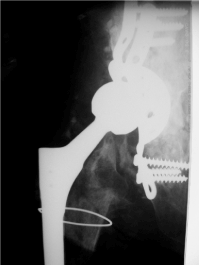

In July 2007 the patient suffered from pain of the right hip. X ray of the right hip showed radiolucent lines in zone I - III according to DeLee of the acetabular component (Figure 2).

Figure 2. X-ray of the right hip (ap view): Total hip arthroplasty with a stable stem with no signs of loosening, destruction of the greater trochanter, radiolucent lines in zone I-III according to DeLee of the acetabular component

ROM was limited with extension / flexion 0/0/90°, abduction/adduction 10/0/10°, external rotation / internal rotation 10/0/10°. Scar was normal. There were no radiolucent lines concerning the stem. Two stage revision surgery due to septic loosening was performed elsewhere. In January reimplantation of the right hip was performed reconstructing of the acetabulum with a reinforcement device and a Wagner revision stem and 3 cerclage wires elsewhere. 3 weeks later rerevision was performed due to recurrent dislocation using a longer head.  Another dislocation occurred 2 months later with shortening of the right leg which was external rotated (Figure 3). Closed reduction was performed. 3 months later x-ray control was performed to evaluate the bony transplants (Figure 4). 2 years later in 2010 the patient presented herself again at our institution with no pain concerning her right hip but inability to walk; since several months she was using a wheel chair there was no history of trauma. The right leg seemed to be shortened and external rotated. ROM was painfully limited.

Figure 3.  X-ray of the right hip (ap view) shows a dislocated wagner revision stem with 3 cerclage wires and reconstruction of the acetabulum with massive bone transplants.